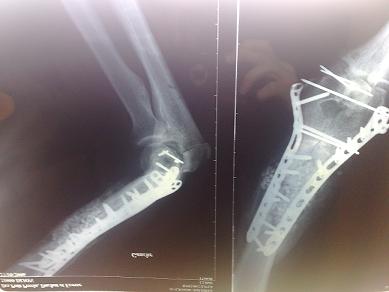

oui accident de moto en 2006, fraca du coude gauche, a l epoque j avais frolé l emputation!

et j ai subit il y a 3 semaine a paris cette opération par un super professeur, la sixième entre autres greffe de tendon d achile(prelevé sur donneur ) pour me faire un tendon tricipital

voici les radios après mes premières opérations